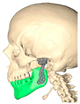

| Gender/Age (Years) | Image | MIO Preop (mm) | MIO at 6 Months (mm) | VAS Preop | VAS at 6 Months | Functional Result | Aesthetic Result | Complications |

|---|---|---|---|---|---|---|---|---|

| F/36 | ![]() | 25.9 | 36.4 | 8 | 3 | 2 | 2 | None |

| F/49 | ![]() | 15.6 | 35.4 | 9 | 4 | 2 | 2 | Partial left facial palsy |

| F/68 | ![]() | 30.5 | 40.3 | 8 | 3 | 2 | 2 | None |

| F/42 | ![]() | 26.4 | 33.5 | 7 | 2 | 2 | 2 | None |

| Average | 24.6 | 36.4 | 8 | 3 | 2 | 2 |